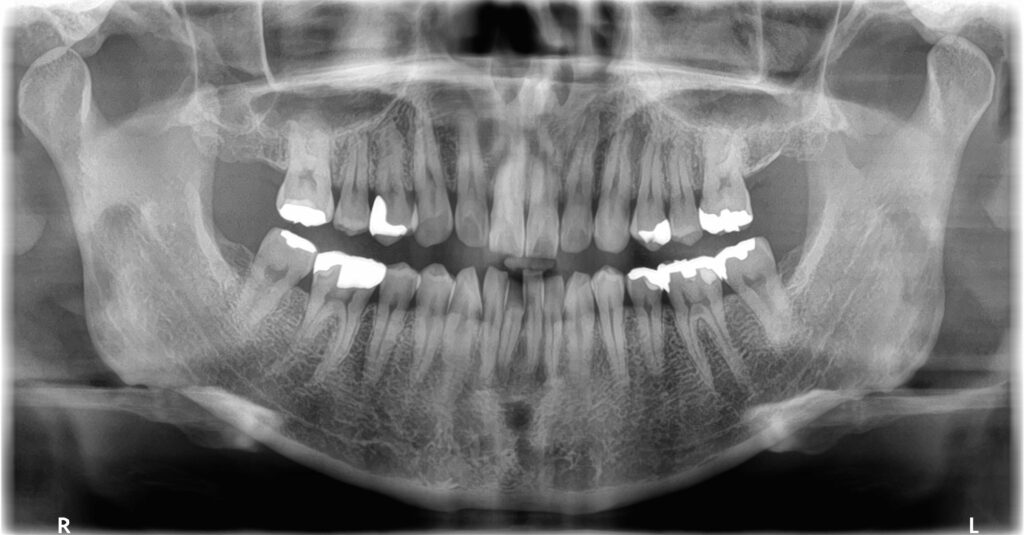

↑従来のレントゲン(2D)

従来のレントゲンは歯や顎の骨、神経、血管などを平面(2D)でしか確認する事ができませんでした。

3Dのレントゲンを撮影することで、2Dのレントゲンでは確認できない歯の根の形態や病巣の広がり、骨の厚み等を診断が可能になります。